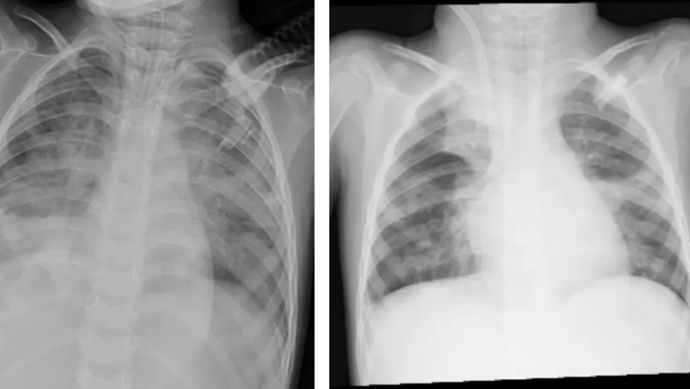

图源 河南省儿童医院(左图为ECMO上机前,肺部结构模糊,呈现“白肺”影像表现。右图为ECMO支持治疗5天后,肺部影像清晰度明显改善)